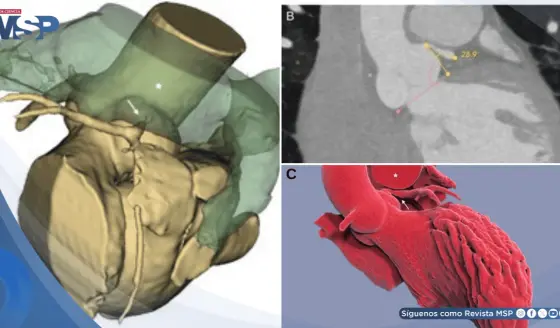

Dolor abdominal severo en paciente de 32 años resultó ser un infarto omental y no apendicitis